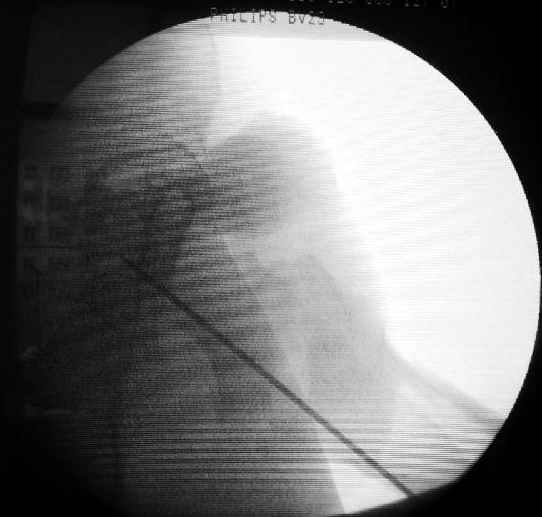

Да, сейчас это и у нас самый напрашивающийся выбор. Сделали гвоздем ChM, картинки в приложении.